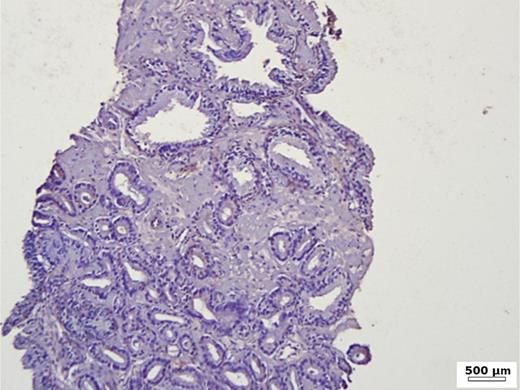

In the group of patients without carcinoma, the vast majority exhibited BSP expression of less than 1%. Twenty-nine out of thirty patients had a value below 5% (Table 1). One patient showed a BSP expression of 9%; however, the expression was observed only in basal cells in a condition of basal cell hyperplasia combined with chronic inflammation (Fig. 1). BSP expression in prostate tissue without carcinoma and without basal cell hyperplasia is shown in Figure 2.

Immunohistochemistry in prostate tissue without carcinoma and without basal cell hyperplasia.